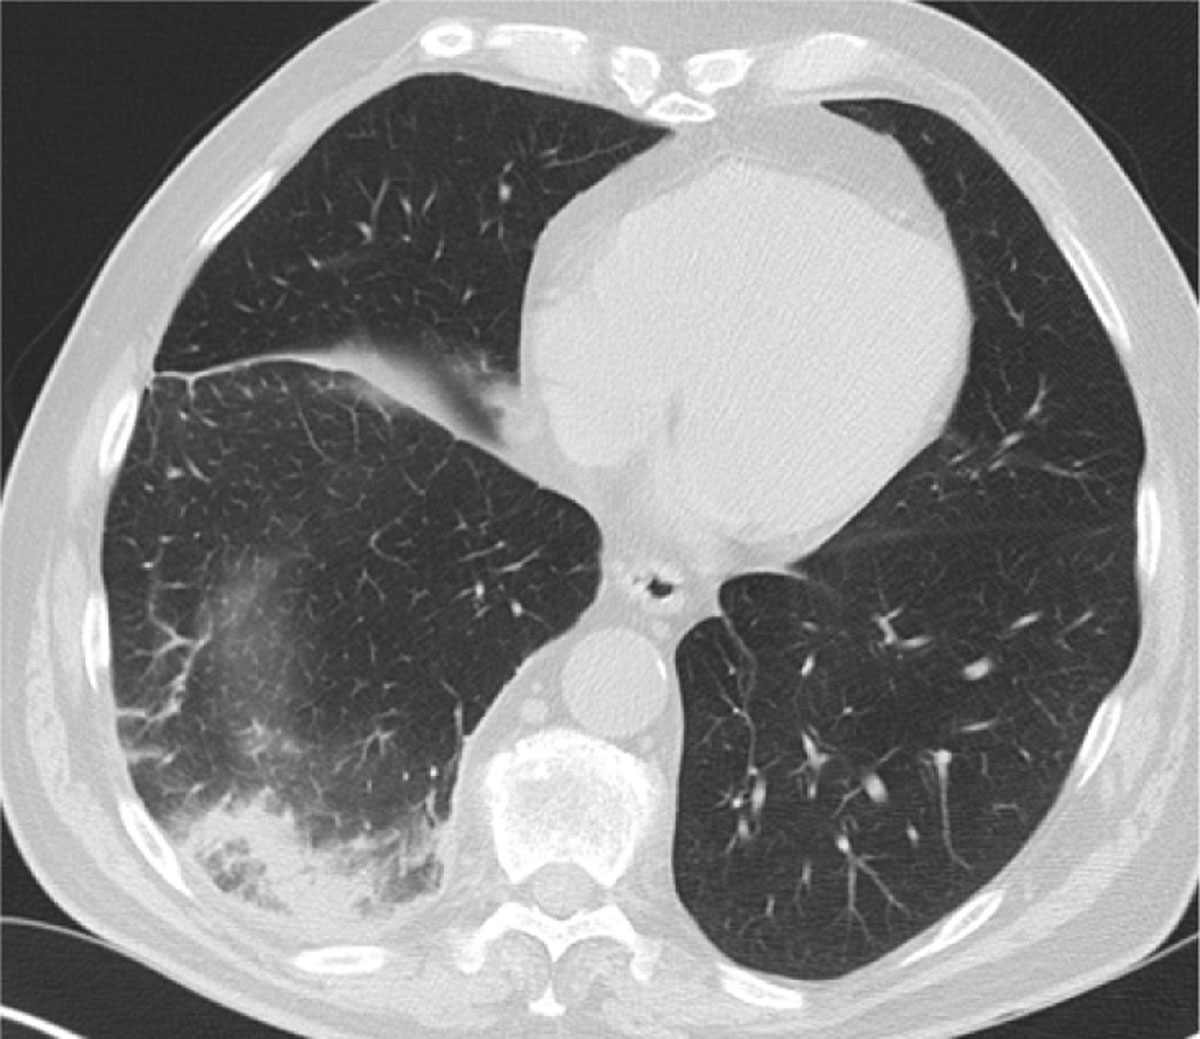

However, during admission the cough persisted, the need for oxygen therapy increased, and the patient complained of right flank pain. A HRCT was performed which showed round consolidation, located subpleural in the dorsobasal part of the RLL accompanied by an atoll sign (Figure 2). Lung infarction was suspected by the radiologist and, after consulting the clinician, a CT angiography was performed. This showed (sub)segmental acute pulmonary thromboembolisms (Figure 3) and confirmed a lung infarction in the RLL. A low-molecular-weight heparin was started at therapeutic dose.

Figure 2

HRCT with a ground-glass opacity surrounded by a crescentic consolidated zone (RHS) in the subpleural space of the RLL.

This case signifies the RHS as an indirect parenchymal sign on plain CT for the diagnosis of pulmonary infarction, even in patients with no suspicion of PE. Although the RHS is historically suggestive for organising pneumonia, its localisation and distribution can suggest other diagnoses.

A retrospective study by Marchiori et al. [4] found multiple findings that can suggest a pulmonary infarction on plain CT: 1) the presence of internal areas of low attenuation; 2) located in the peripheral regions of the lower lobes; 3) most often single lesions and no more than two lesions; and 4) the presence of pleural effusion in half of the cases. They also report the importance of integrating clinical features: if the patient is immunocompromised, one must also suspect an invasive fungal infection. Others also found that these lesions are usually subpleural, in the posterior parts of the lower lobe, and affect the right lobe more often than left [3].

In retrospect, we can identify an enlarged right inferior hilum (Fleischner sign) with adjoining tapering of the pulmonary vessel (knuckle sign) on the initial CXR (Figure 1) [15]. These signs often coincide and are highly specific for PE, yet of low sensitivity. Other examples are the Westermark sign or Hampton-hump [156], whilst not clearly visible in this case. The initial diagnosis in our patient was delayed due to the recent history of pneumonia and since D-dimers were not measured. Luckily, when chest CT was finally performed, presence of the atoll sign in the subpleural, dorsobasal part of the RLL was quickly picked up as a possible lung infarction and CT angiography was advised, confirming the diagnosis.

This case report shows that although the RHS or atoll sign is most commonly associated with cryptogenic organizing pneumonia, it is still important to consider differential diagnoses. A HRCT with a RHS, especially when solitary and/or in the dorsobasal parts of the lower lobes, should raise suspicion of a pulmonary infarction and should warrant further investigation, preferably with a CT pulmonary angiography.